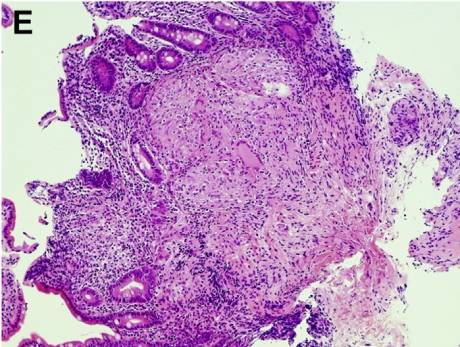

上、下消化道内镜检查时均予活检,结果显示:非干酪样上皮细胞肉芽肿(图E、F)。